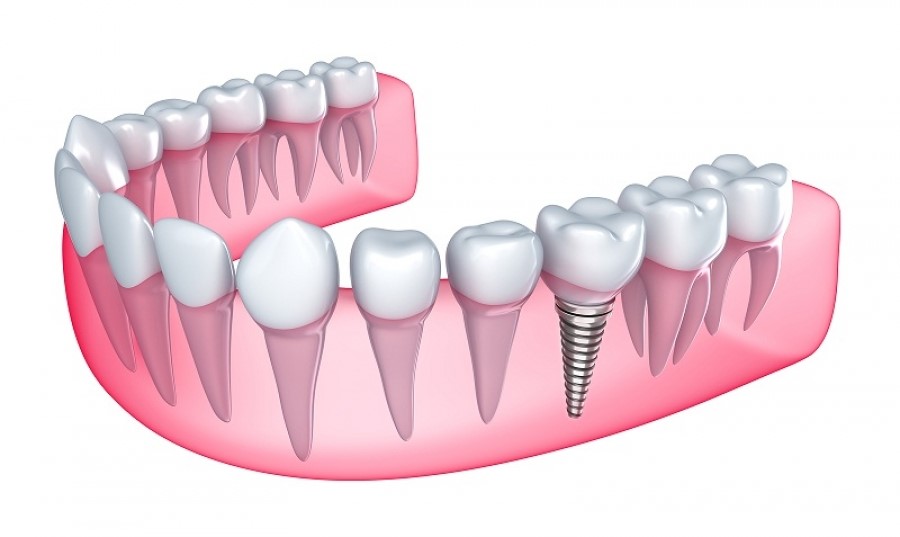

کشیدن دندان های آسیب دیده و جایگزین کردن آن ها برای سلامت بدن و سلامت سایر دندان ها هم ضروری است. زمانی که دندان های طبیعی تان را به دلایل مختلف از دست می دهید، نه تنها با مشکلات متعددی روبرو می شوید بلکه کارایی سایر دندان ها را هم ممکن است از دست بدهید. برای برخی ها، از دست دادن دندان و خالی ماندن جای آن در دهان کمی ناراحت کننده است اما اگر چنین شرایطی درمان نشده رها شود مشکلات زیادی برای دهان تان ایجاد خواهد کرد. ایمپلنت های دندانی به شما کمک می کنند ظاهر و حس بهتری داشته باشید، اعتماد به نفس از دست رفته تان را پس بگیرید و کیفیت زندگی تان را بهبود ببخشید.

بیش از 50 سال است که دندانپزشکان از ایمپلنت برای جایگزین کردن دندان های از دست رفته استفاده می کنند و می توانند عملکرد دهان و دندان هایتان را به سرعت به شما باز گردانند شما به یک لبخند زیبا نیاز دارید و ایمپلنت کردن می تواند در رسیدن به این هدف کمک تان کند. در ادامه سعی می کنیم برخی از مزایای ایمپلنت دندان را با هم مرور کنیم.

یکی از بزرگ ترین مزایای ایمپلنت تغییر ظاهری و محافظت از استخوان ها و پیشگیری از تغییر شکل بیشتر ساختارهای صورت است. در چنین شرایطی است که می توان به بهبود ظاهر امیدوار بود. زمانی که بیشتر دندان های طبیعی با مشکل مواجه می شوند یا می افتند، چیزی در استخوان فک باقی نمی ماند تا رشد استخوان ها را تحریک کند. بدن انسان به این شرایط پاسخ می دهد و فکر می کند استخوان فک دیگر لازم نیست از دندان ها حمایت کند. همه این موارد دست در دست هم می دهند تا ظاهر و چهره شما را تغییر دهند. حالا باید منتظر بمانید و شاهد تغییر ساختار صورت تان همچون چین و چروک لب، چین و چروکی که اطراف دهان ایجاد می شود و مشکلاتی که در چانه تان به وجود می آید باشید.

این موارد در کنار هم ظاهر شما را پیرتر از آنچه که هست نشان می دهند. با ایمپلنت دندان، چین و چروک و افتادگی ساختار صورت رخ نمی دهد و شما را بیست سال از آنچه که هستید جوانتر نشان می دهد. حتی زمانی که تنها یکی از دندان هایتان می افتد باز هم زیبایی چهره تان در طولانی مدت خدشه دار می شود. به همین خاطر ایمپلنت کردن می تواند بهتر از سایر روش های سنتی همچون بریج دندان برایتان مفید باشد. همه این مواردی که بیان کردیم برای دندان های جلویی تان از اهمیت بیشتری برخوردارند چون محافظت از این بخش برای داشتن یک ظاهر طبیعی ضروری است.

همانطور که در بخش قبلی ذکر کردیم ایمپلنت نزدیک ترین نوع دندان به دندان های طبیعی شماست. زمانی که کل دندان هایتان را به کمک این شیوه بازسازی می کنید ظاهر و لبخند زیباتری خواهید داشت و می توانید از عملکرد طبیعی دهان نیز لذت ببرید. هر چیزی که در دهان شماست حالا ظاهر طبیعی خواهد داشت و هیچ کس متوجه ایمپلنت هایتان نخواهد شد.

از دیگر مزایای ایمپلنت می توان به حفاظت از دندان های سالم مجاور اشاره کرد زیرا استفاده از سایر روش های سنتی برای جایگزین کردن دندان، دندانپزشک را مجبور می کند دندان هایی که در نزدیکی و مجاورت دندان اسیب دیده هستند را بسابد تا بتواند بریج مخصوص را سر جای خود قرار دهد. زمانی که ساختار طبیعی دندان از بین رفت بازگردانی و جایگزینی آن دشوار خواهد بود. دندان های مصنوعی که معمولاً به جای یک یا چند دندان از دست رفته به کار می روند به دندان مجاور می چسبند و بر روی آن ها فشار وارد می کنند. به هنگام استفاده روزمره از این دندان ها، ساختار به کار رفته در آن ها مدام جلو و عقب می رود و باعث می شود روزهای بسیار سختی را تجربه کنید.

با گذشت زمان این امر بافت های باقی مانده لثه را دچار آسیب می کنند و حتی مشکلات بیشتری را به وجود می آورند. به همین خاطر استفاده از ایمپلنت می تواند گزینه بهتری باشد چون در این شرایط دندان های طبیعیِ مجاور دست نخورده باقی می ماند و آسیبی به آن ها وارد نمی شود. ایمپلنت دندان به شما اجازه می دهد تا جایی که ممکن است از دندان های طبیعی خود محافظت کنید.